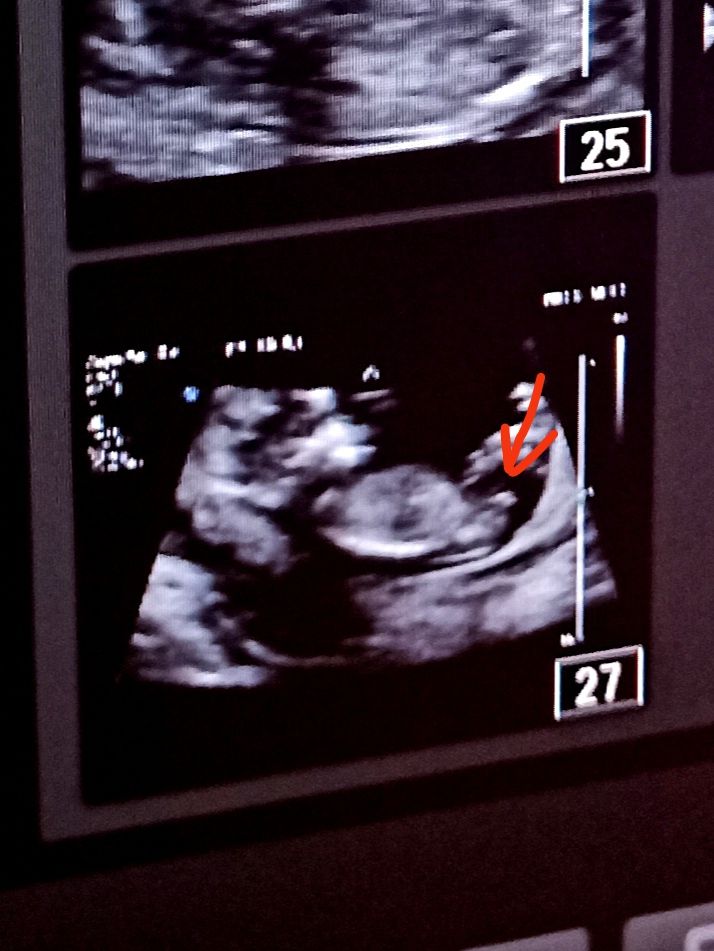

Малыш лежит как бы боком, ножки вытянутые, видео пяточки слева. Справа вот торчок - это уже без вариантов мальчишка? Врач сказала мальчик конечно) С сыном между

Сегодня ходила на УЗИ, и впервые столкнулась с такой ситуацией. На одном кадре у малыша прям торчок был вверх, это и сама знаю - мальчик, так как уже мальчик есть и там так же было. Потом часто проскальзывала картина между ножек - ничего не было, а потом когда в профиль под конец, врач сказал - видите, сейчас не очень информативно, малыш мог сог